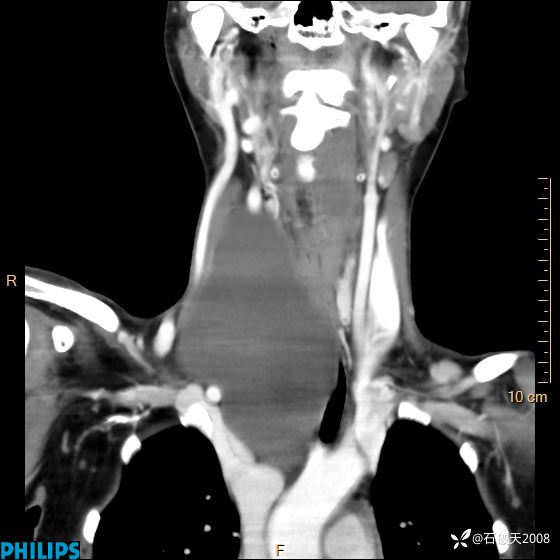

冠状位

静脉期